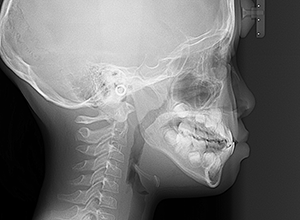

X-Ray

X-Ray所見

セファロ所見 下顎骨体部は大きく下顎枝は前傾しており下顎角は鈍角であった。上顎骨はやや劣位で奥行きがなく下顔面高は高くなっていた。

家族歴や側貌所見、下顎は大きいもののANBは2°でSellaに対して下顎頭は後方に位置していることなどから将来的に重度な下顎前突へ移行することは少ないと予測できた。